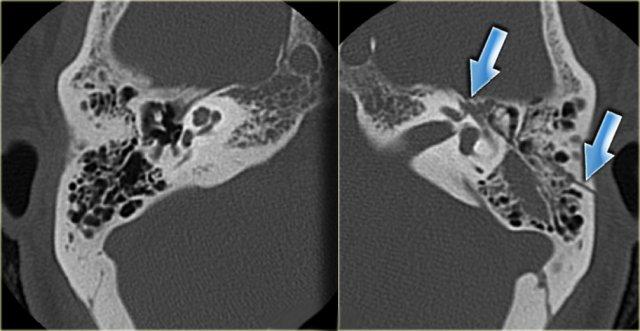

Bên trái là các ảnh cắt coronal của cùng một bệnh nhân.

Bên phải, động mạch cảnh trong tách biệt hoàn toàn với tai giữa (mũi tên xanh dương).

Bên trái, động mạch cảnh trong đi xuyên qua tai giữa (mũi tên đỏ).